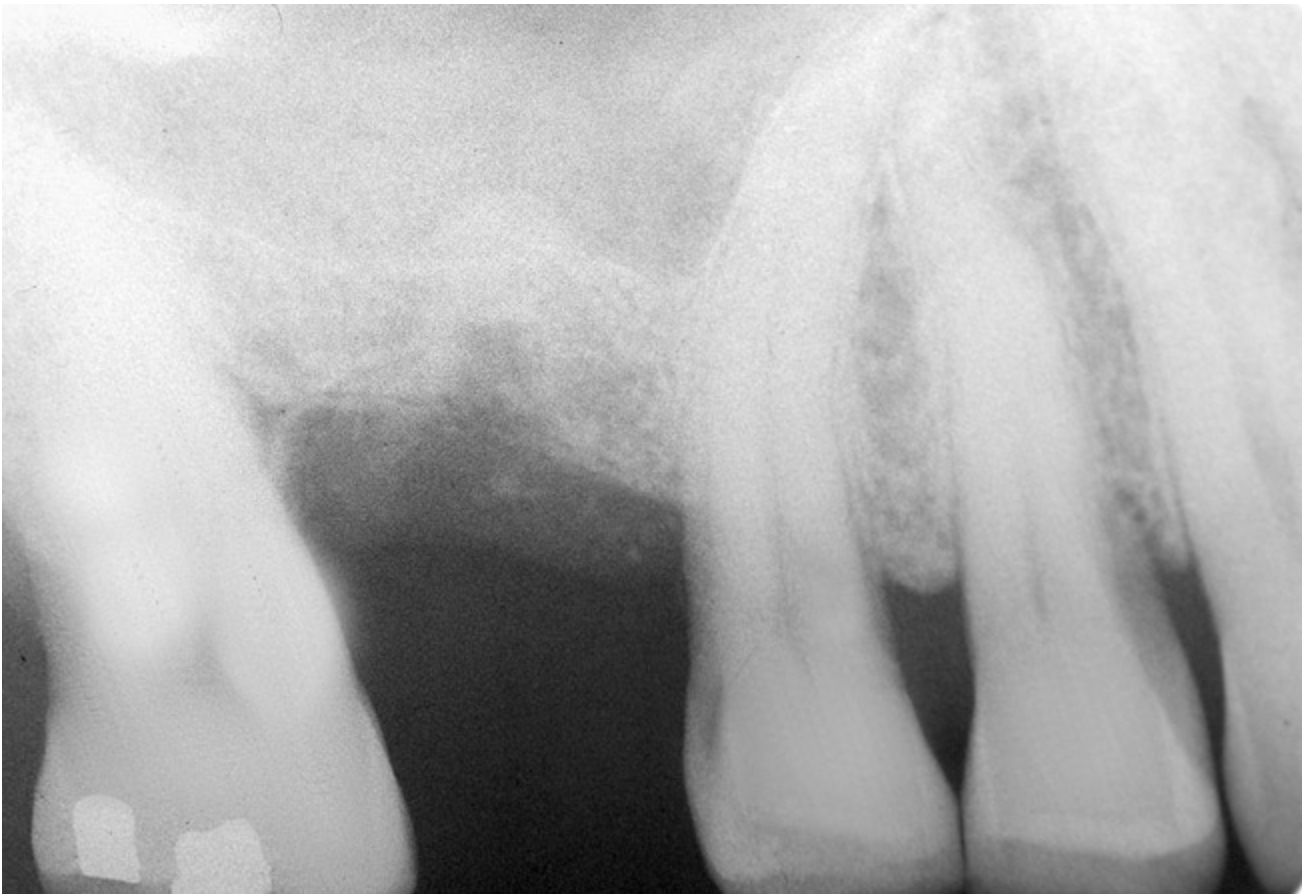

The sinus floor elevation technique can be used when a tooth is extracted and there is not enough bone height to support an immediate implant (Figure 8, Figure 9 and Figure 10, Figure 11).32

Figure 8  At site No. 13 the second bicuspid had a hopeless prognosis; it was to be extracted and replaced with an implant after a transcrestal sinus floor elevation.

Figure 8

Figure 9: After the extraction, a 2.1-mm twist drill was used to drill within 1 mm of the subantral floor. A guide pin was placed and a radiograph was taken to ascertain if the drill stopped within 1 mm of the subantral floor.

Figure 9